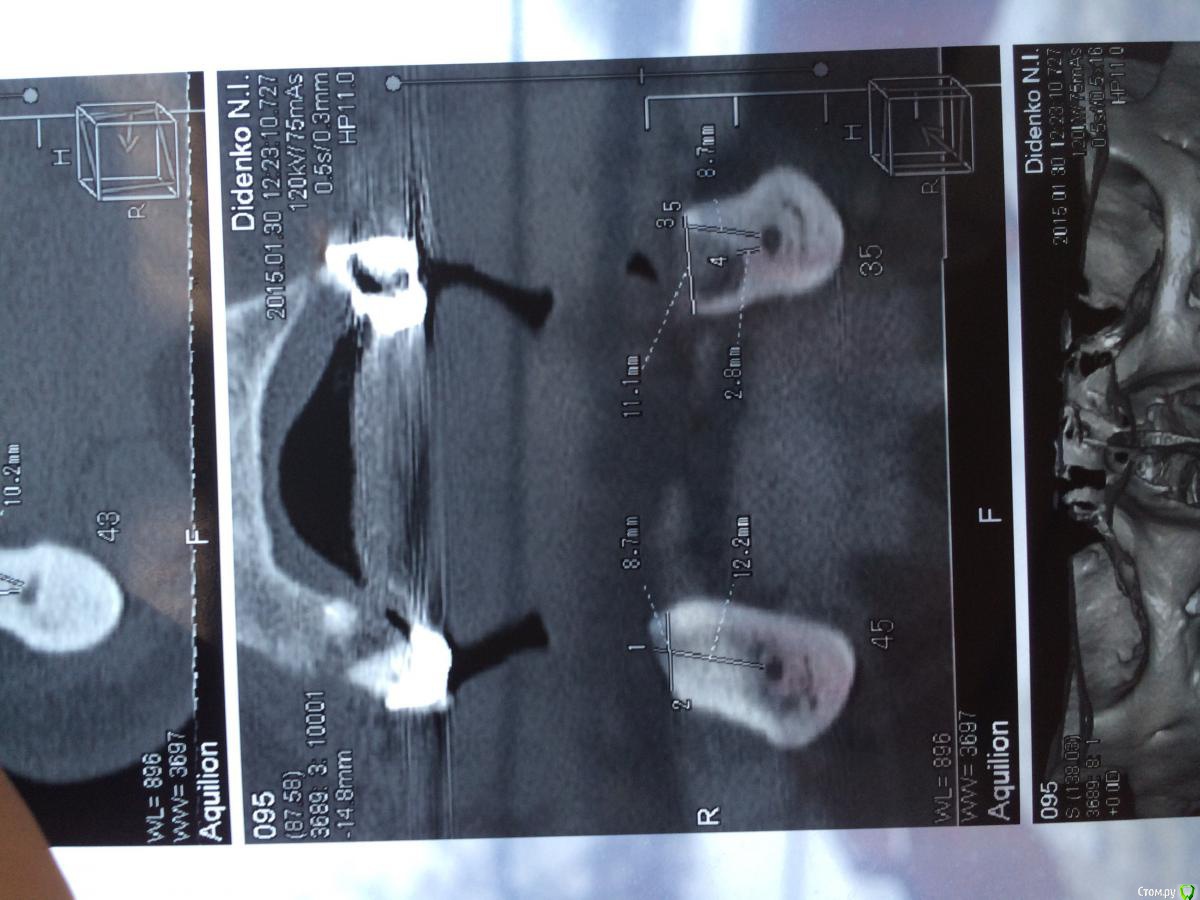

urseva19.05.10 Опубликовано 31 января, 2015 Поделиться Опубликовано 31 января, 2015 Коллеги, в каких позициях на ваш взгляд целесообразнее поставить имплантаты желательно без НКР ( пациент ограничен во времени) что бы в последствии протезироваться съемным протезом на локаторах? На верх не смотрите там все ясно Спасибо! Ссылка на комментарий

kriokov Опубликовано 31 января, 2015 Поделиться Опубликовано 31 января, 2015 1. выравнивайте гребень2. Позиции 34 , 32, 42, 44, если болты позволяют их субкрестально поставить , то притопите, и ушиться бы двурядно, Ссылка на комментарий

urseva19.05.10 Опубликовано 1 февраля, 2015 Автор Поделиться Опубликовано 1 февраля, 2015 1. выравнивайте гребень2. Позиции 34 , 32, 42, 44, если болты позволяют их субкрестально поставить , то притопите, и ушиться бы двурядно, 1. Всё-таки считаете без НКР не обойтись?2. С 32,42 понятно, а если в области 36,46 установить не будет ли лучше фиксация протеза, да и условия вроде позволяют. Как думаете? Ссылка на комментарий

kriokov Опубликовано 1 февраля, 2015 Поделиться Опубликовано 1 февраля, 2015 1. Всё-таки считаете без НКР не обойтись?2. С 32,42 понятно, а если в области 36,46 установить не будет ли лучше фиксация протеза, да и условия вроде позволяют. Как думаете?1. не знаю, лучше бы просто ОПТГ глянуть и четко срезы в межментальном отделе2. Я не делал так , ставил всегда по просьбе ортопеда в межментальном Ссылка на комментарий

колесников Опубликовано 1 февраля, 2015 Поделиться Опубликовано 1 февраля, 2015 тут подойдёт постановка по типу ,,всё на 4ёх,, ,обходя ментальные.костные пики во фронте надо нивелировать и материал всётаки оставить. Ссылка на комментарий

АнтонТЛТ Опубликовано 9 февраля, 2015 Поделиться Опубликовано 9 февраля, 2015 Потихоньку задумываюсь об этом. В области каких зубов думаете без нкр получиться?ширина достаточная, так что практически в любом месте можно поставить короткие имплантаты Ссылка на комментарий